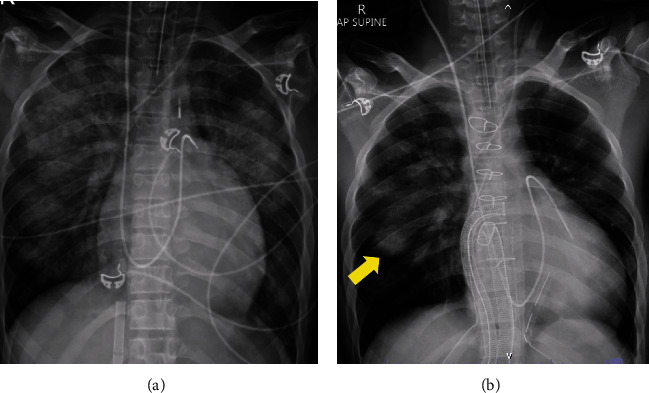

虽然活动性感染通常是心脏移植手术前的禁忌症,但一名被诊断为扩张型心肌病的 16 岁男子在脓毒性休克和心源性休克的情况下,仍患有活动性可能侵袭性肺曲霉菌病和细菌性肺炎,并成功接受了心脏移植手术。

Although active infection is generally a contraindication before an orthotopic heart transplant, a 16-year-old man diagnosed with dilated cardiomyopathy successfully underwent an orthotopic heart transplant despite having active probable invasive pulmonary aspergillosis and bacterial pneumonia in the presence of septic and cardiogenic shock.